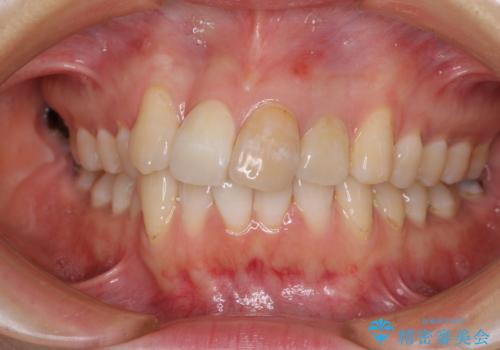

前歯のクロスバイトと治療が必要なむし歯 矯正とセラミックの総合歯科治療